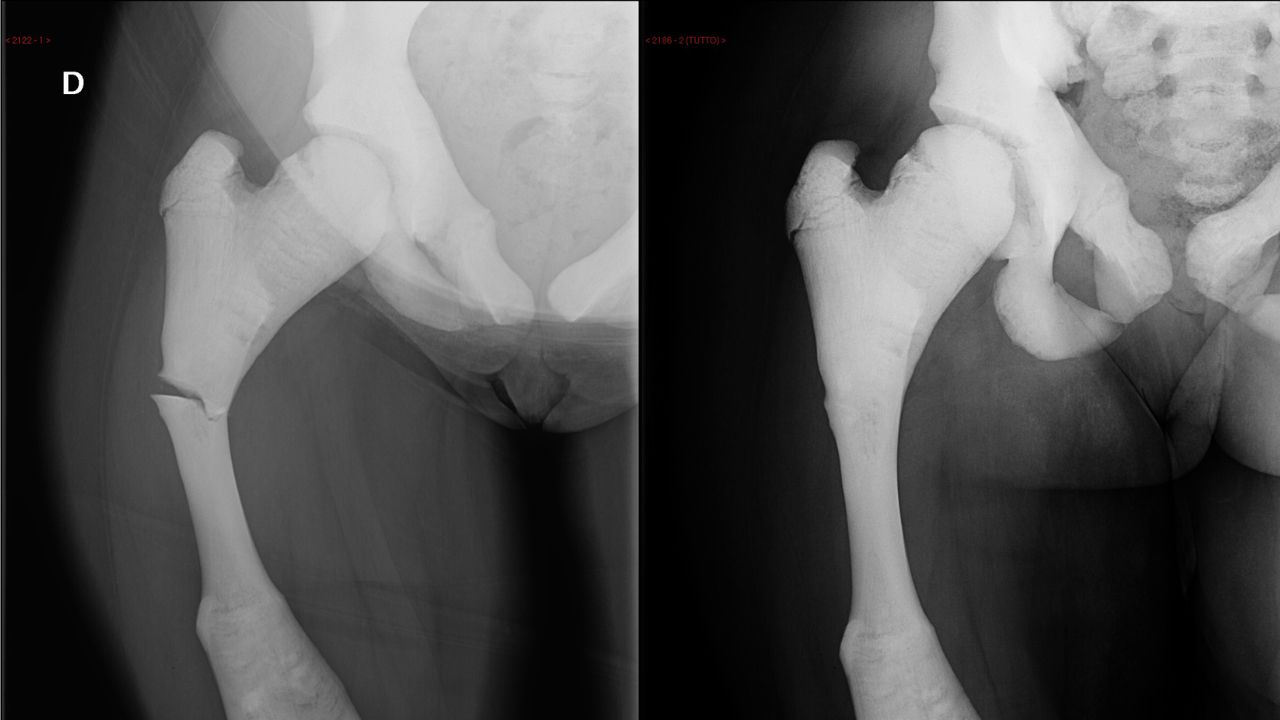

شکستگی پاتولوژیک می‌توانند در هر استخوانی از بدن رخ دهند، اما معمولاً در استخوان‌های بزرگی همچون ستون فقرات، لگن، ران، استخوان بازو و ساق پا مشاهده می‌شوند.

• رادیوگرافی: این آزمایش تصاویر عمومی از استخوان‌ها را ارائه می‌دهد و می‌تواند شکستگی‌ها و تغییرات ساختاری را نشان دهد.